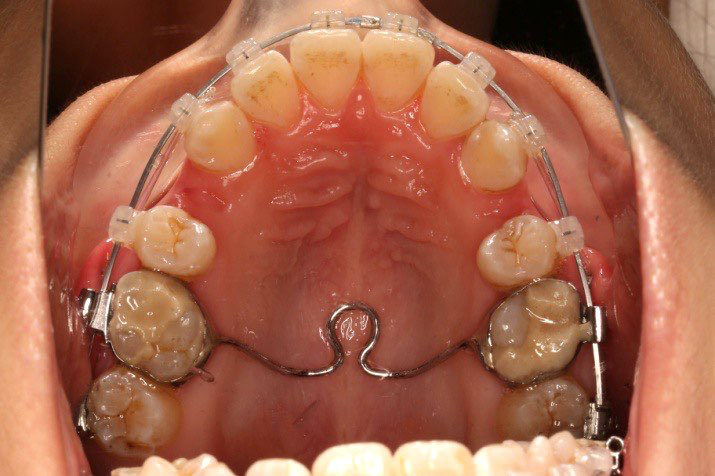

2017.07.25

2017.07.25  上前牙加颈部弹力线

2017.10.07

2017.10.07  继续关间隙,下颌使用水平关间隙

下颌磨牙通过powerarm直立效果明显,下颌整平效果明显